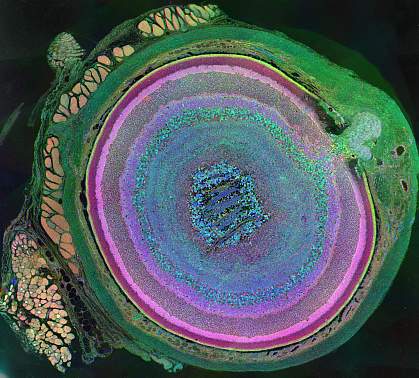

Age-related macular degeneration (AMD) is a common eye problem in older adults. It’s caused by inflammation that damages the macula, the part of the eye that controls sharp, straight-ahead vision. AMD is currently the most common cause of vision loss in adults over the age of 50 worldwide.